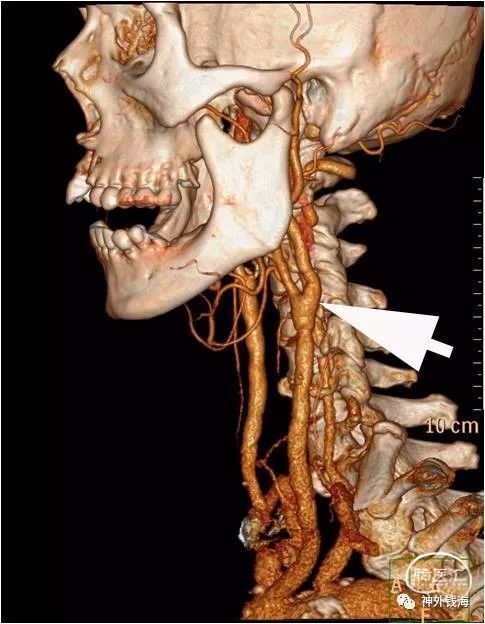

上图可见颈动脉分叉部膨隆,内部为斑块,如箭头所示。